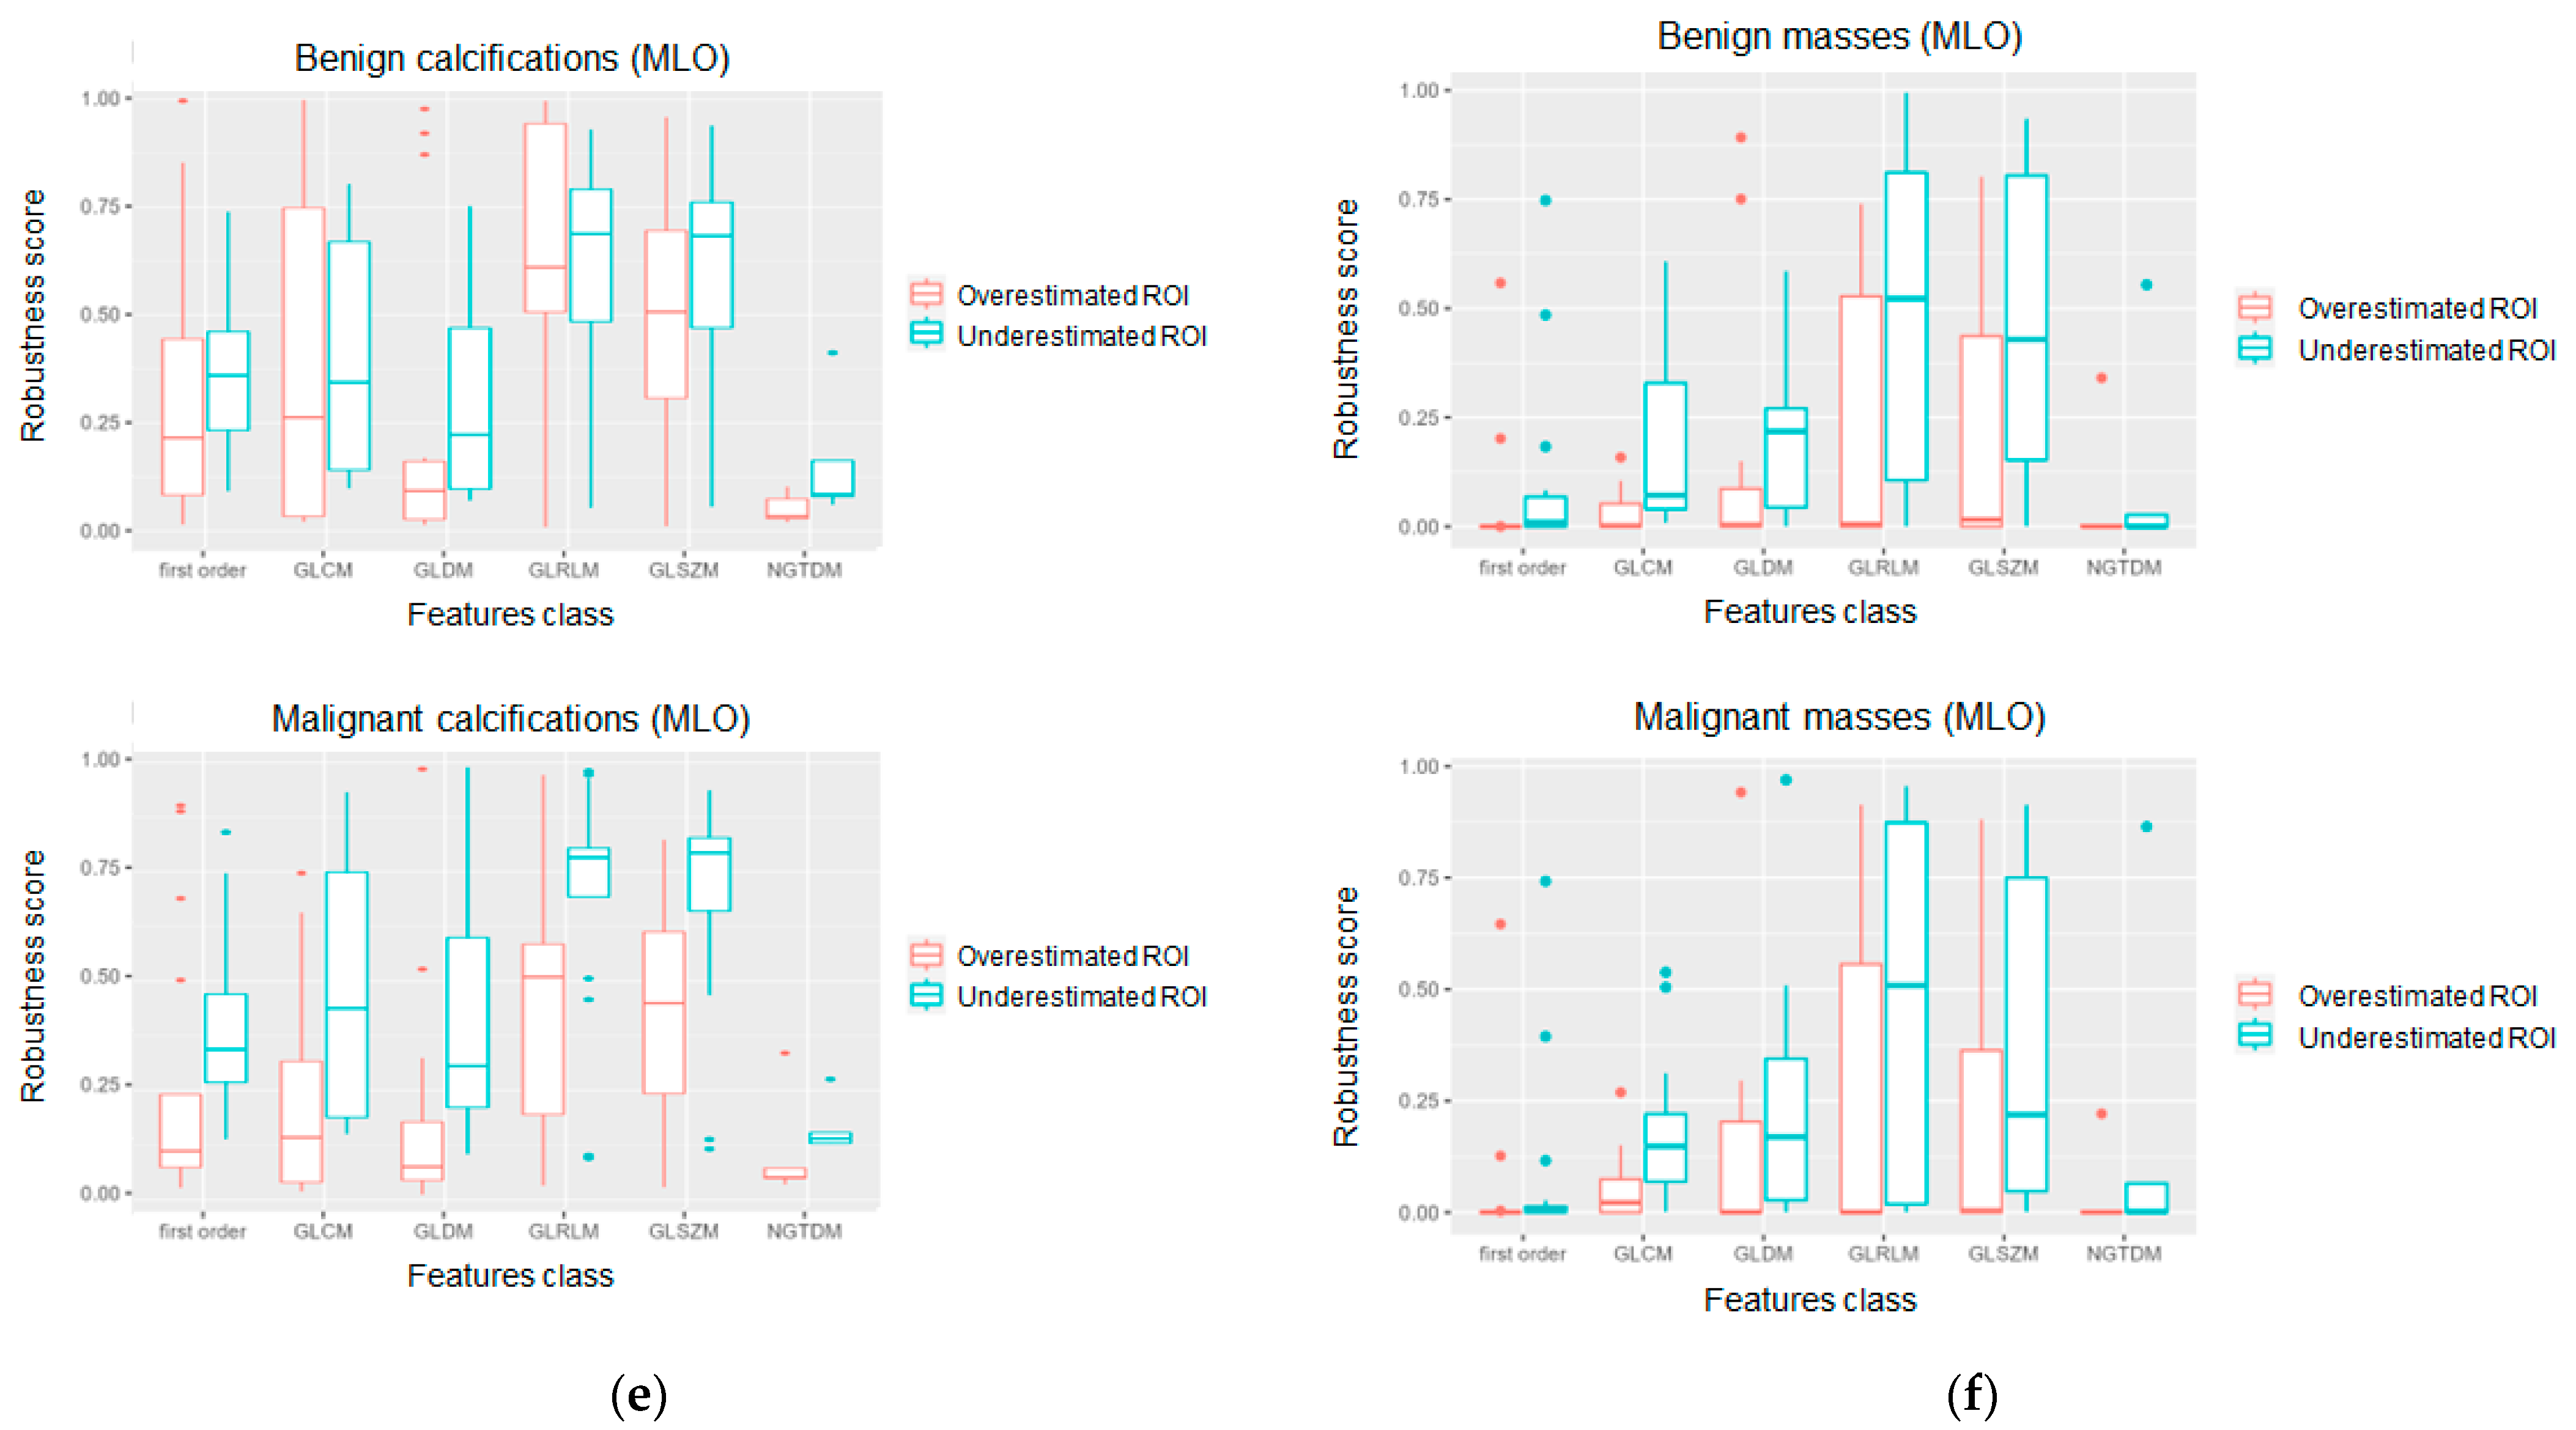

3. Results

4. Discussion